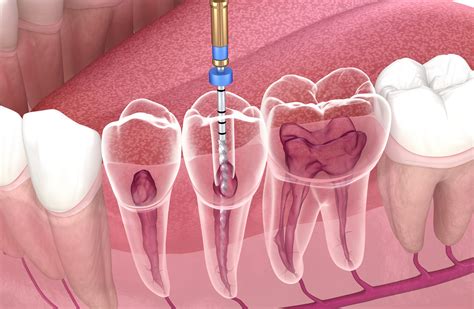

¿Has vuelto a sentir dolor en una muela o diente tratado con endodoncia después de varios meses? Aunque no es lo habitual, puede suceder. Un diente tratado con endodoncia no debería doler de forma continua después de su recuperación inicial. Si las molestias aparecen al cabo de unos meses, es señal de que algo puede estar fallando en el tratamiento o que existe una nueva infección. Aunque durante el tratamiento de endodoncia dental se elimina el nervio del diente, el dolor puede aparecer por la inflamación de los tejidos que rodean la raíz, como el ligamento periodontal o el hueso.

El objetivo del tratamiento endodóntico es eliminar la infección que ha afectado al nervio y conservar el diente sin dolor. Si esto no se logra en un tiempo razonable, estamos ante un tratamiento fallido. Además, es posible que los síntomas se manifiesten incluso años después del tratamiento. Un diagnóstico claro solo puede establecerlo tu dentista mediante exámenes complementarios como radiografías, pruebas de sensibilidad y estudios clínicos.

Un tratamiento de conducto o endodoncia, es un procedimiento odontológico bastante común hoy día. Pero, como en toda intervención, hay cierta posibilidad de que surjan complicaciones en una endodoncia. Es por ello que aquí te enseñaremos qué tipo de problemas puede surgir en una endodoncia, y cuáles son sus síntomas. De esta manera podrás identificar algún problema luego del tratamiento y acudir al especialista a tiempo.

- Prolongación del dolor: Esta es la complicación más común en una endodoncia, y esto generalmente sucede cuando quedan conductos del diente sin sellar. Es por ello que, si el dolor continúa luego del tratamiento, será necesaria una nueva exploración de la pieza dental para determinar si existe otro conducto que aún no se ha tratado.

- Perforación radicular: Esto puede surgir mientras se hace la endodoncia y se endurece la búsqueda de conductos radiculares. Generalmente, el especialista utiliza un material denominado MTA, para sellar la grieta provocada. En la mayoría de casos la evolución suele ser favorable, aunque se recomienda vigilar en los meses siguientes la endodoncia.

- Fractura de instrumento: Durante una endodoncia es posible que alguno de los instrumentos con los que se realiza la intervención se rompa y parte del mismo quede dentro del conducto de la raíz. En este caso, el especialista debe tratar de extraer el material con un instrumento más fino y volver a limpiar el conducto. Claro, este inconveniente es muy poco visto, sobre todo si acude a un especialista con experiencia, buena formación, y que emplea materiales de primera calidad.